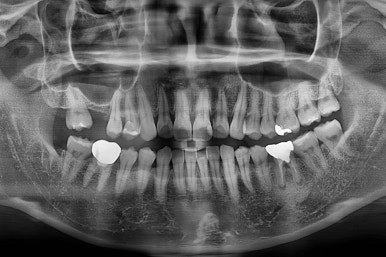

오늘 부산치아교정비용 키다리아저씨치과에서 소개해 드릴 환자분은 어금니가 없어서 임플란트를 앞두고 해당 부분 임플란트를 위한 교정을 진행했던 분이며, 더불어 아래 앞니쪽이 삐뚤어 부분교정을 하셨던 분입니다.

어금니가 문제였습니다.

윗니 어금니가 하나 없는 상태였고요.

어금니가 없이 지낸지 꽤 시간이 흐른터라 뒤쪽 어금니가 앞으로 쓰러져 공간을 잠식하고 있었습니다.

X-ray로 봤을 때 빈 공간에는 여러 가지 문제가 있었는데요.

뒷니가 쓰러졌다.

공간이 잠식 당했다.

어금니 위쪽 공기주머니가 잇몸뼈를 갉아먹으면서 잇몸뼈가 매우 얇아져있다.